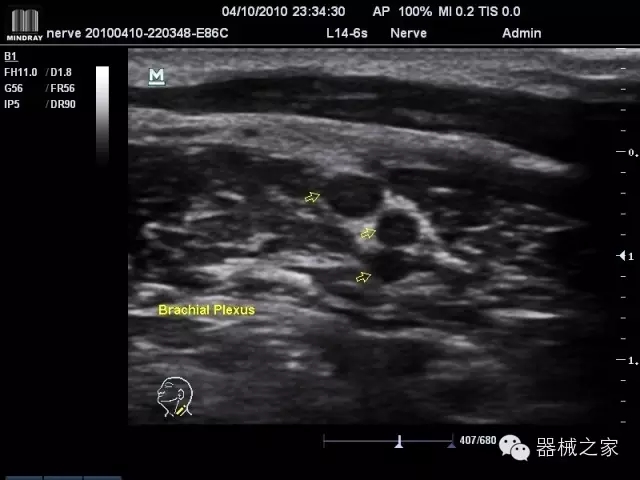

臨床圖片賞析

產(chǎn)品特點(diǎn)